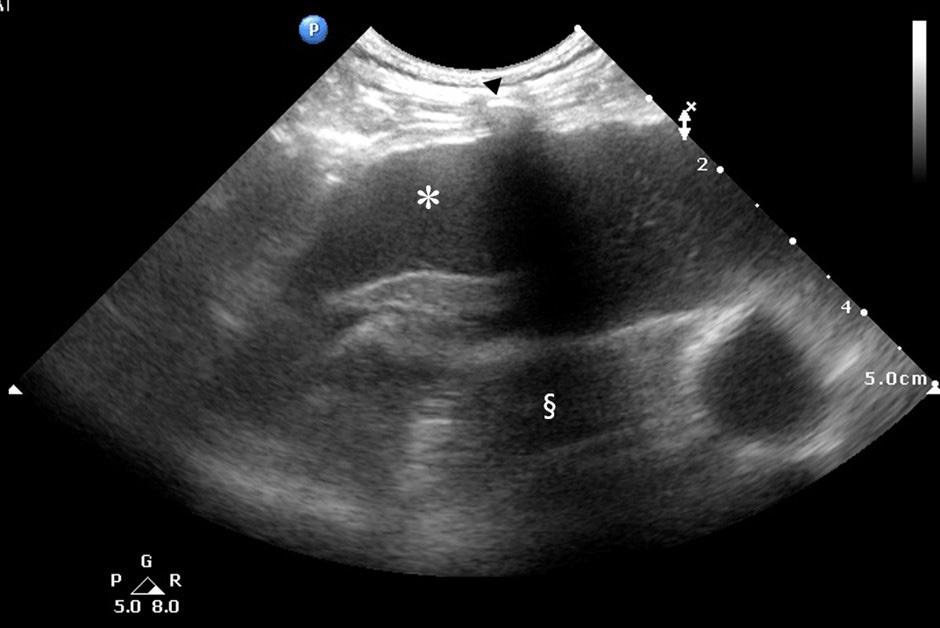

Fig. 1. 본 증례에서 흉부 초음파 검사를 통해 확인된 흉수 소견

흉강 내에서 저에코성 흉수(*)가 관찰되었으며, 갈비뼈(화살촉 표시)에 의해 초음파가 통과하지 못해 형성된 고에코성 음영(§)이 함께 확인되었습니다. (Pleural effusion confirmed by ultrasonography of the thoracic cavity in this case.

Hypoechoic pleural fluid (*) is observed in the thoracic cavity, and an echogenic shadow (§) is observed due to the impermeability of ultrasound to the ribs (arrow head).)